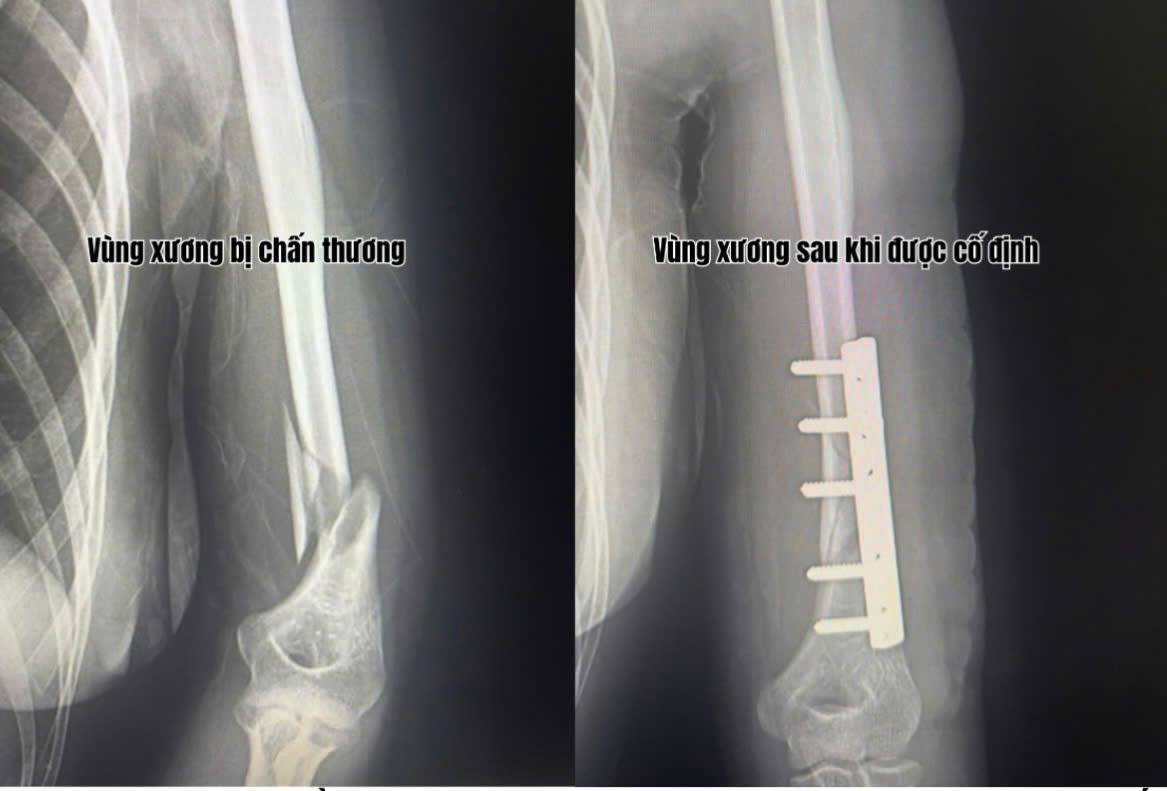

Trong thời gian gần đây, Khoa Ngoại – Trung tâm Y tế Thị xã Quảng Yên liên tiếp tiếp nhận nhiều trường hợp chấn thương vùng cánh tay, khớp khuỷu do tai nạn sinh hoạt và lao động. Các ca bệnh đều có đặc điểm gãy xương phức tạp, tổn thương lan đến khớp, đòi hỏi phẫu thuật chính xác và xử trí kịp thời để tránh biến chứng dính khớp, cứng khớp hoặc mất chức năng vận động.

Trước yêu cầu chuyên môn cao, đội ngũ bác sĩ chấn thương chỉnh hình của Trung tâm, do BSCKII Đỗ Văn Cường trực tiếp phẫu thuật, đã triển khai kỹ thuật kết hợp xương (KHX) vùng cánh tay – khớp khuỷu bằng hệ thống nẹp vít chuyên dụng dưới hỗ trợ của máy C-arm hiện đại.

Việc ứng dụng công nghệ hình ảnh tăng sáng trong mổ giúp định vị chính xác ổ gãy, kiểm soát toàn bộ quá trình nắn chỉnh và cố định, đảm bảo xương được đặt đúng vị trí, khớp được bảo tồn tối đa.

Nhờ kỹ thuật chính xác và quy trình phẫu thuật an toàn, các bệnh nhân sau mổ đều có xương cố định vững, khớp khuỷu vận động sớm, giảm đau nhanh, hồi phục chức năng tốt. Việc tập phục hồi vận động sớm được bác sĩ hướng dẫn ngay tại giường bệnh, giúp hạn chế tối đa nguy cơ teo cơ và cứng khớp.